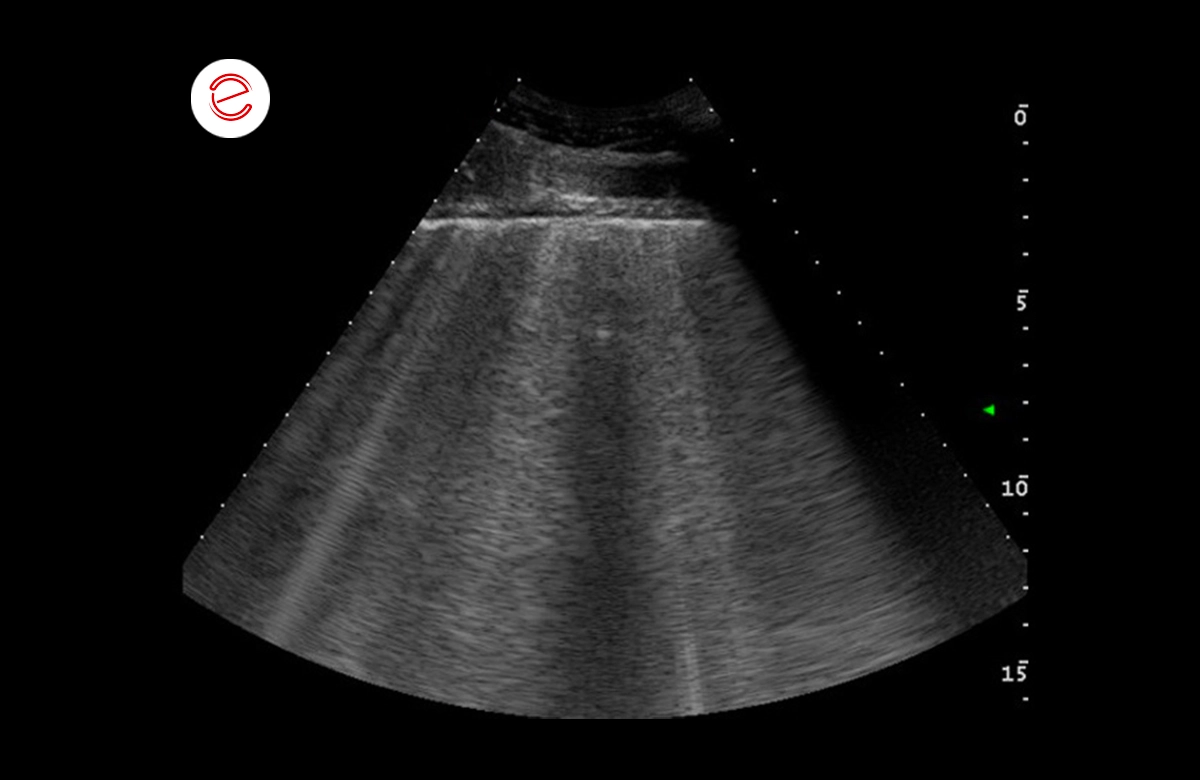

The images show numerous comet tail artefacts widespread on both the right and left side that are suggestive of pulmonary edema.